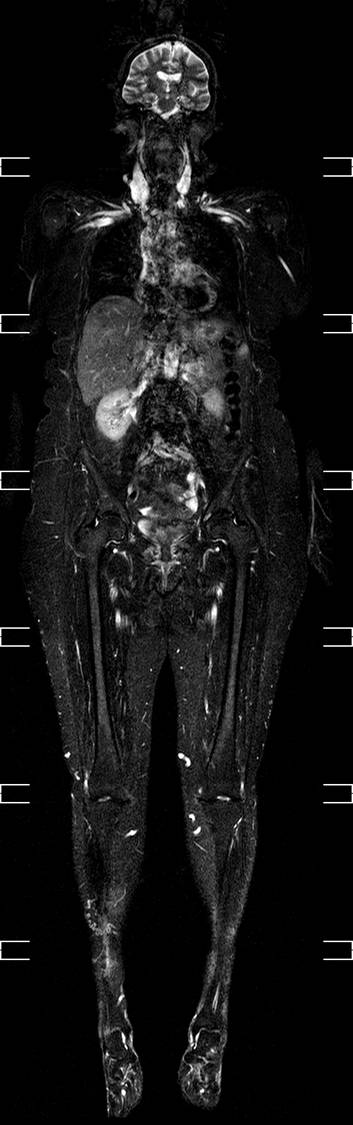

MR-skanner, helkrops

Helkrops MR-skanning. Det tager under 30 minutter at nå fra top til tå 2 gange. Man laver en fedtsupprimeret T2-vægtet skanning , hvor man får fremstillet, hvor der er vand i kroppen.